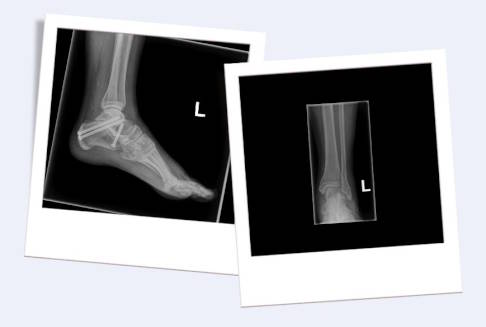

Röntgenbild einer subtalaren Arthrodese von der Seite (links) und von vorne (rechts). Die eingebrachten Schrauben verbinden das Sprungbein mit dem Fersenbein. © Gelenk-Klinik